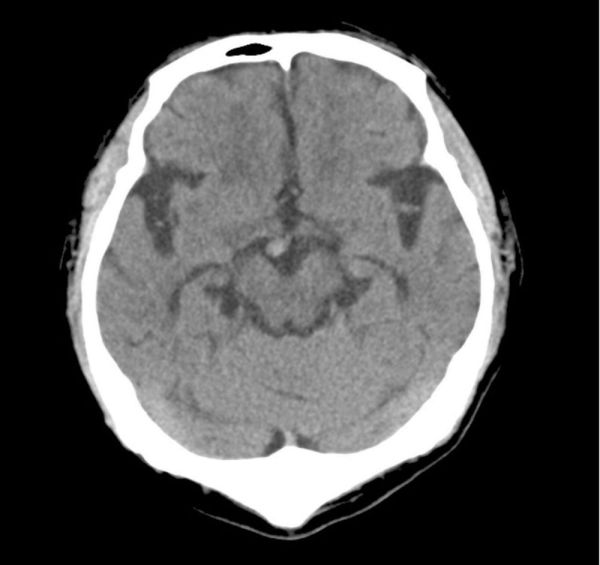

For this project, I collaborated with Dr. Yoshinobu Ishiwata of the Department of Radiology at Yokohama City University Hospital, as I do not have a background in medicine.. I observed CT scan reading sessions and conducted joint analyses based on the data he generously shared with our research team. At first glance, I could not tell at all which areas of the CT scans indicated incidental findings such as tumors or blood clots. In contrast, Dr. Ishiwata was immediately able to identify and point out areas of concern. For reference, I would like my readers to take a look at Figure 1.

Can you tell where the abnormality is in the image?

Figure 1. CT head scan with an incidental finding

Click below to view the answer. The incidental finding is circled in red.

https://bit.ly/3F2HEfq